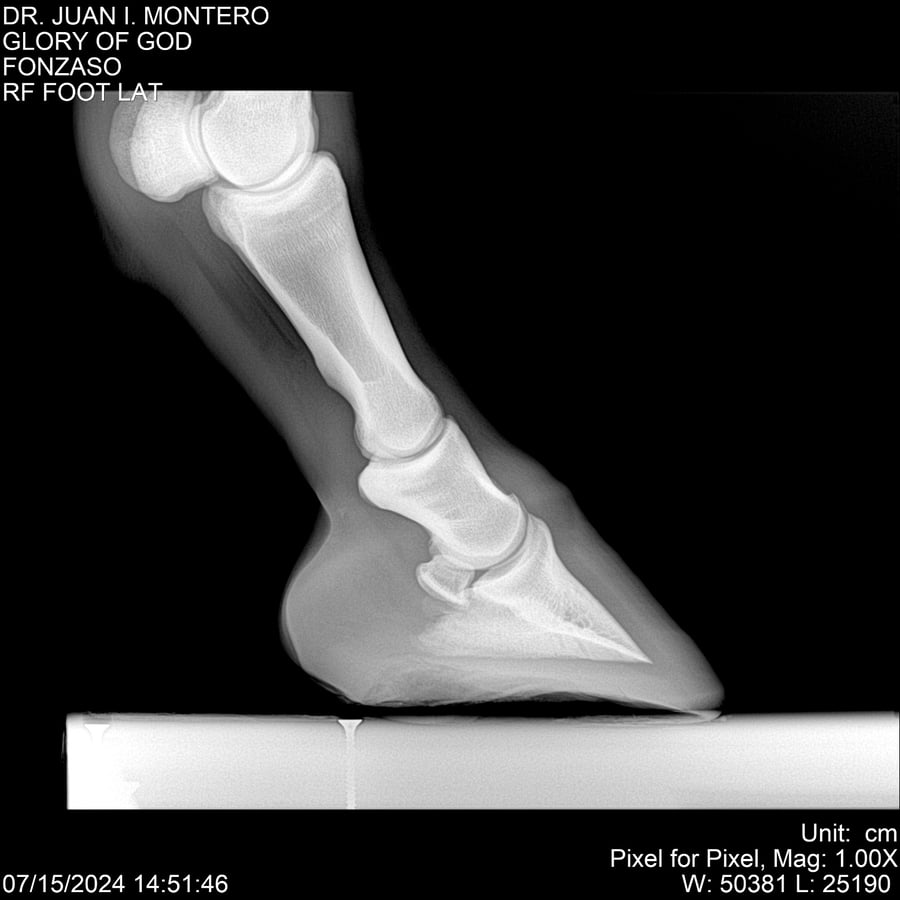

LOTE 10, GLORY OF GOD 🔥 🔥 🔥 Lote Anterior Volver al remate Lote Siguiente Ficha Contacto Montevideo - Ficha del Lote Identificador: #281389 Categoría: Yeguarizos Montevideo - 115 Visualizaciones ClicData Contacto Empresa: Abelenda N. R., Walter Hugo Nombre*: Teléfono* : E-mail* : Mensaje Enviar Registrese gratis Este contenido Exclusivo está disponible sólo para usuarios registrados Ingresar